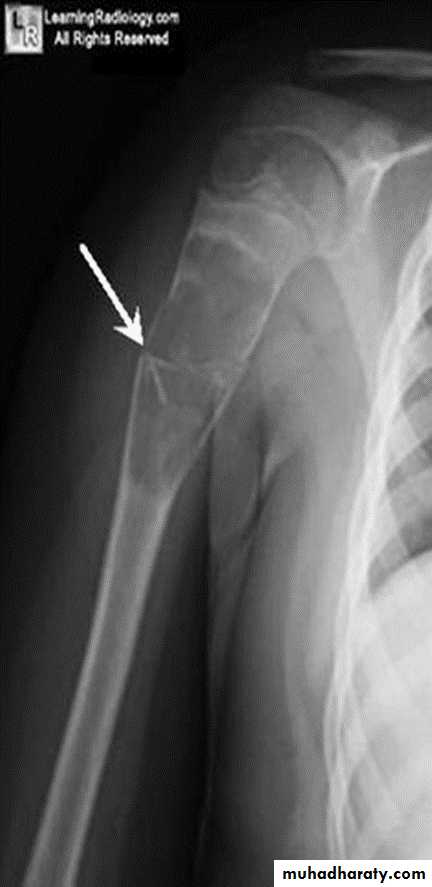

Area of bone destruction or sclerosis with ill-defined margins, wide zone of transition & periosteal reaction with or without cortical destruction & soft tissue swelling.Osteosarcoma :

Age: 5-20-yrs, elderly with Paget's disease.Site: metaphyseal around the knee joint.

Findings:

Lytic

Blastic

Mixed

Poorly defined bony destruction.

Sun ray speculation (periosteal reaction).

Elevation of the periosteum at the margin producing the so called Codman's triangle.

Cortical destruction.

Soft tissue swelling.